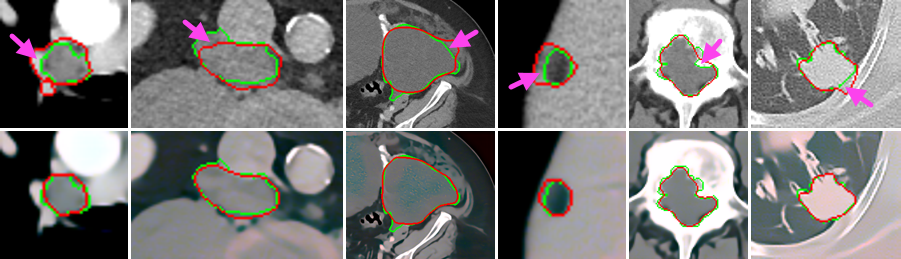

Figure 3: Visual examples of lesion segmentation produced by HNN from the OG images (1stsuperscript1𝑠𝑡1^{st} row) and their combinations with enhanced SGAN images (2ndsuperscript2𝑛𝑑2^{nd} row). The manual and automatic segmentation boundaries are delineated with green and red curves, respectively. Incorrectly segmented regions when using OG images that are corrected when using SGAN images are highlighted with pink arrows. Best viewed in color.

Figure 3 shows several visual examples of lesion segmentation results using HNN on original images and their combinations with the images produced by SGAN. From Fig. 3, the segmentation results on the combined images are closer to the manual segmentations than the ones on only original images. This intuitively demonstrates that the enhanced images produced by the SGAN model is helpful for lesion segmentation.